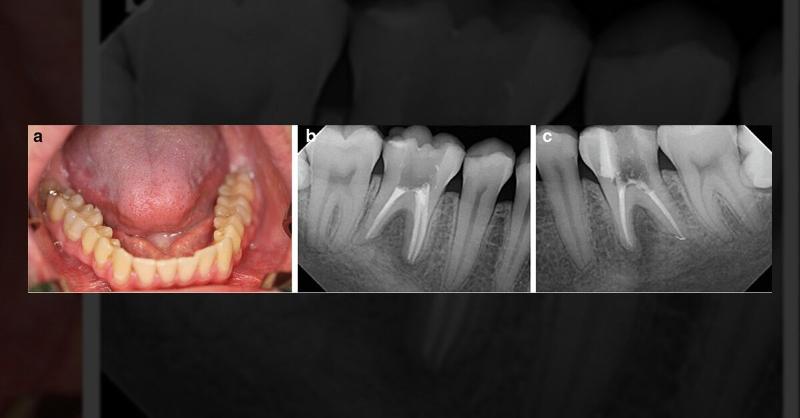

A 28-year-old healthy male presented with apical periodontitis affecting teeth 36 and 46. Despite ongoing endodontic treatment, both teeth showed worsening apical osteolysis. Neither tooth had caries, trauma, or periodontal issues, and the patient was asymptomatic. Clinical examination revealed increased tooth mobility and bifurcation, with probing